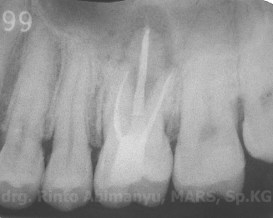

Berikut penampakan setelah dilakukan pengisian…

Hasil ronsen nya pun menunjukkan pengisian yang hermetis dan adaptasi tambalan yang baik…